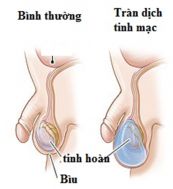

Tràn dịch tinh mạc là tình trạng tụ dịch ở một hoặc cả hai bìu ở trẻ em hoặc nam giới. Nếu tràn dịch tinh mạc ở cả hai bìu thì thường nguyên nhân nằm trong bệnh cảnh phù toàn thân. Ngược lại, nếu chỉ tràn dịch tinh mạc một bên (chỉ một bên bìu to ra) thì thường do bệnh lý tại chỗ hoặc do các bất thường cấu trúc giải phẫu vùng bẹn – bìu. Cùng eLib.VN tìm hiểu bài viết dưới đây để hiểu rõ hơn về bệnh lý này nhé!